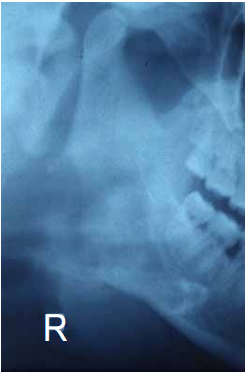

5 甲醫師正在為病患拔除智齒,結果卻發現 27 gauge 的長針頭斷裂在病人口腔中,如下圖之 X 光片所 示,甲醫師此時最可能是在做那一條神經的阻斷術? (A)長頰神經 (B)舌神經 (C)下齒槽神經 (D)後上齒槽神經

6 承上題,該斷裂的針頭最有可能是在穿刺下列那一條肌肉時造成斷裂? (A)外翼肌 (B)內翼肌 (C)嚼肌 (D)顳肌

7 承上題,該斷裂的針頭最有可能是斷在下列那一個組織間隙? (A)顎下間隙(submandibular space) (B)頦下間隙(submental space) (C)舌下間隙(sublingual space) (D)翼顎間隙(pterygomandibular space)

8 承上題,患者呈現的早期症狀應為何? (A)呼吸困難 (B)頰部腫脹 (C)牙關緊閉 (D)舌頭升起